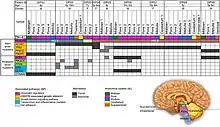

The definitive genetic marker of a diffuse midline glioma is H3K27me3 loss. Diffuse midline gliomas have three known subtypes:[23]